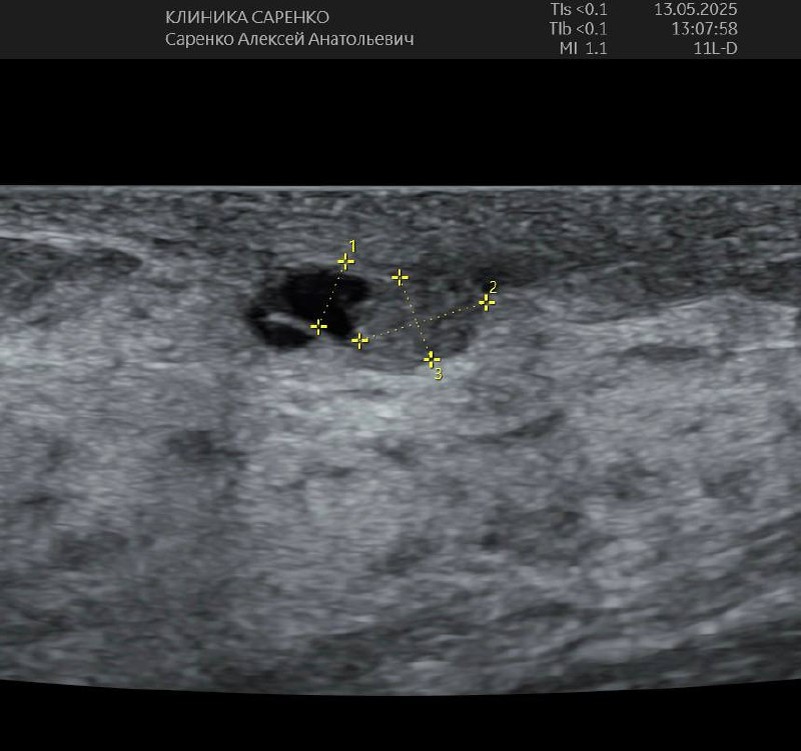

Внутрипротоковая папиллома молочной железы (болезнь Минца)

✅ Молодая женщина, жалоб нет

✅ На УЗИ обнаружили кисту в молочной железе, делали пункцию - всё хорошо

🟢 Два года наблюдается, делается УЗИ

✅ Видят черный овал, значит киста - домой

✅ Но это не киста, это проток и в нём папиллома!